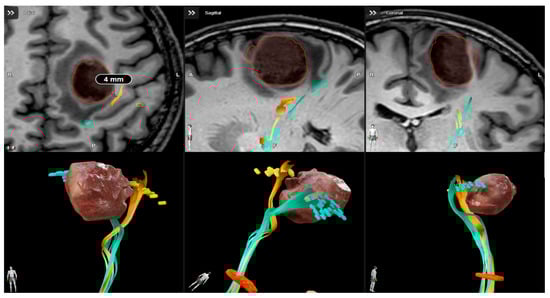

The Weight of Eloquence in Motor Area Glioblastoma: Oncologic Outcome After nTMS-Guided Surgical Resection

Luca Sartori, Samuel Luciano Caliri, Roberto Colasanti, Pietro Dalla Zuanna, Nicola Bresolin, Valentina Baro, Pietro Ciccarino, Francesco Volpin, Franco Chioffi, Luca Denaro and Andrea Landi

NeuroSci 2025, 6(4), 124; https://doi.org/10.3390/neurosci6040124 - 3 Dec 2025

Background: Glioblastomas (GBMs) in eloquent areas, particularly within the motor system, represent a significant surgical challenge due to the risk of postoperative neurological deficits. This study evaluates the effectiveness of a structured preoperative protocol, including nTMS-guided motor mapping, to optimize surgical outcomes and minimize neurological deficits, with a particular focus on the timing of adjuvant oncological therapy initiation. Methods: A retrospective analysis was conducted on 44 GBM patients, divided into two groups: 11 with motor area lesions (group A) and 33 with non-eloquent lesions (group B). All patients underwent a standardized preoperative protocol. Surgical outcomes (EORs), neurological function (MRC score and KPS index), time to oncological therapy initiation and survival (OS and PFS) were compared between groups. Results: Both groups achieved high rates of GTR without significant differences in EOR (72.7% group A vs. 78.8% group B). Although group A exhibited a higher incidence of postoperative motor deficits, motor function at three-month follow-up was similar between groups. Time to initiation of oncological therapy did not differ between groups (40.6 days group A vs. 41.9 days group B, p = 0.719), highlighting that preservation of motor function helped minimize delays in starting oncological therapy. No significant differences were found in survival outcomes. Conclusions: A structured preoperative protocol incorporating nTMS motor mapping allows for safe and aggressive resection of motor-area GBMs. This approach effectively mitigates the risk of delays in initiating adjuvant oncological therapy, optimizing the patient prognosis. Further studies are needed to explore the long-term benefits of this protocol in both functional and oncological outcomes.

Figure 1